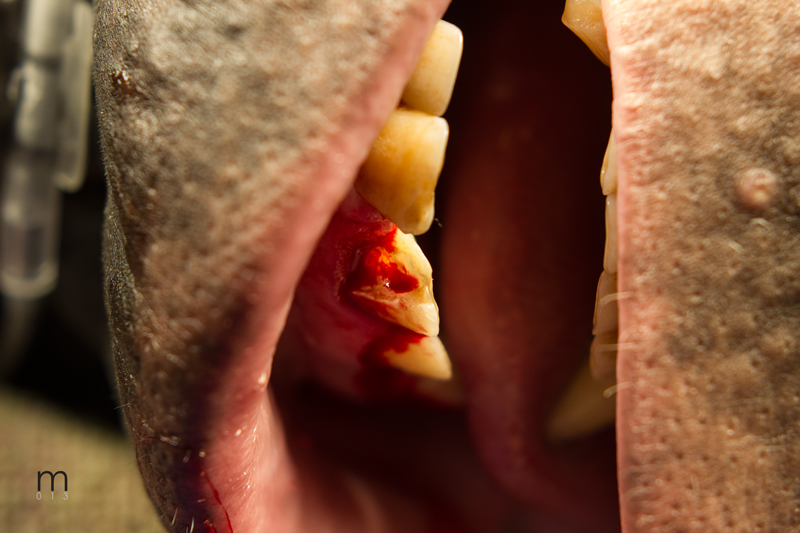

Fistulous chronic drainage tract, found during physical examination, at junction of attached gingiva and buccal mucosa

Fractured maxillary left canine exposed pulp canal